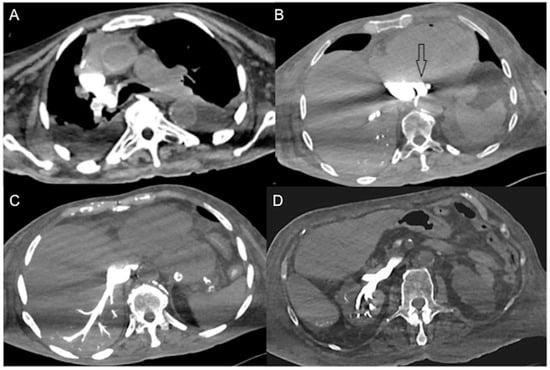

In a normal physiological state, specific gravity has no effect on contrast agent dynamics. In heart failure, CM does not mix with the blood pool and its distribution in the vascular system predominantly depends on its density, injector pressure, specific weight and volume injected [21,39,44]. The dependent layering of injected iodinated CM mainly reflects its higher specific gravity relative to blood in cases of right heart dysfunction and very low cardiac output [47,52]. The consequence is reduced enhancement of the aorta and left-side cardiac chambers with reflux of contrast into the IVC, creating a characteristic horizontal blood-contrast level (“dependent pooling sign” or “IVC contrast level sign”) that could be associated with reflux into the hepatic veins with heterogeneous liver parenchyma enhancement (Figure 3) [18,44,52,66,67].

Figure 3.

CECT axial images of vascular findings in cardiogenic shock. (A) Portal venous phase (delay of 80 s after CM injection) shows IVC contrast level sign (arrow) as well as heterogeneous hepatic enhancement (asterisk) in a 65-year-old man with myocardial infarction and imminent cardiac arrest. (B) Portal venous phase (delay of 85 s after CM injection) shows IVC contrast level sign (arrow) and regurgitation to the right renal vein (empty arrow) in a 63-year-old man with hypotension and acute severe reduction in cardiac index. In comparison to Figure 1D, note the aorta opacification. (C) Portal venous phase (delay of 85 s after CM injection) shows IVC contrast level sign with CM reflux into hepatic VI and VII segments (empty arrow) and (D) contrast level in portal trunk (arrow) in a 68-year-old man with myocardial infarction.

In contrast to horizontal levelling in the IVC layering sign, a vertical IVC levellng sign usually occurs due to physiological retrograde filling of renal veins [68]. Contrast stasis in the right-side cardiac chambers may result in extremely dense chambers and pulmonary arteries with or without a blood contrast level. Vascular stasis will also result in contrast layering within the veins that eventually drain into the right atrium (e.g., brachiocephalic and subclavian veins) (Figure 4).